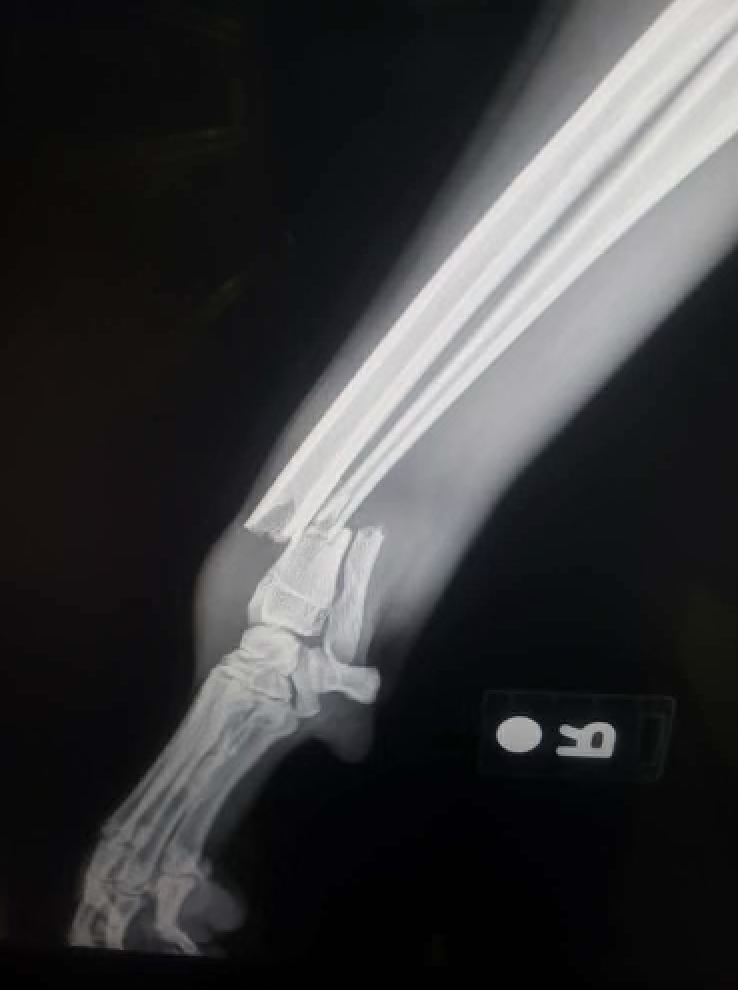

Over the weekend, Pumpkin - also known as Scrump - had a terrible accident while hiking that has resulted in a severely broken leg with breaks in multiple places.